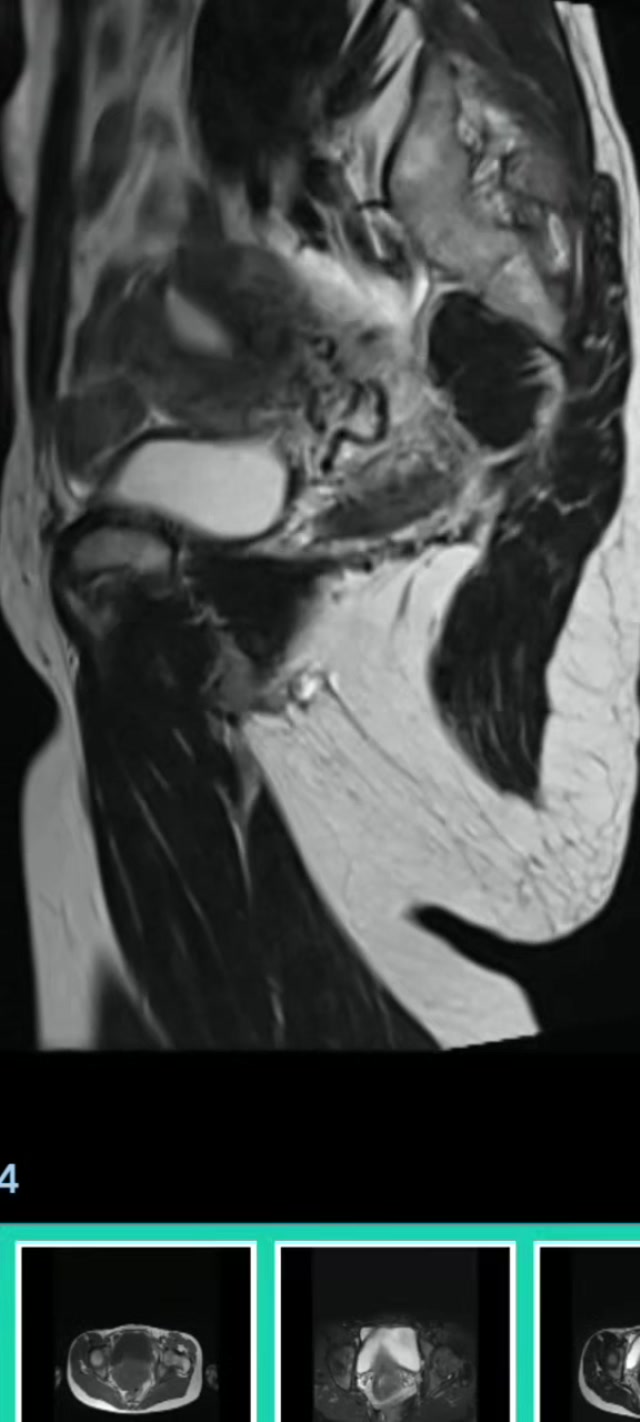

现病史:患者平素月经规律,经型5-7/28-32天,量中,无痛经。一年前检查发现子宫小肌瘤(约3-4cm,具体不详)。近期自觉肛门下坠感来诊,阴超提示子宫后壁肌瘤(大小56*71*42cm),考虑肌瘤较前增大,伴压迫症状,收住院拟手术治疗。